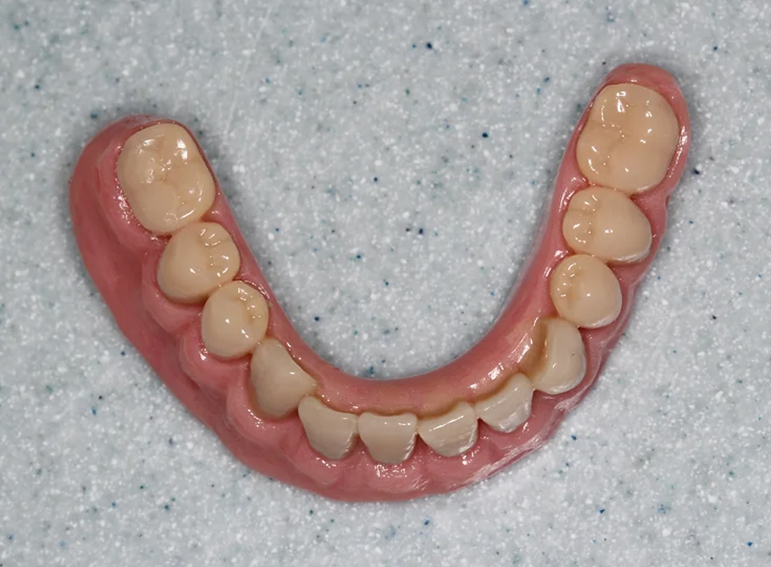

Upper and lower dentures (with implants) after broken jaws.